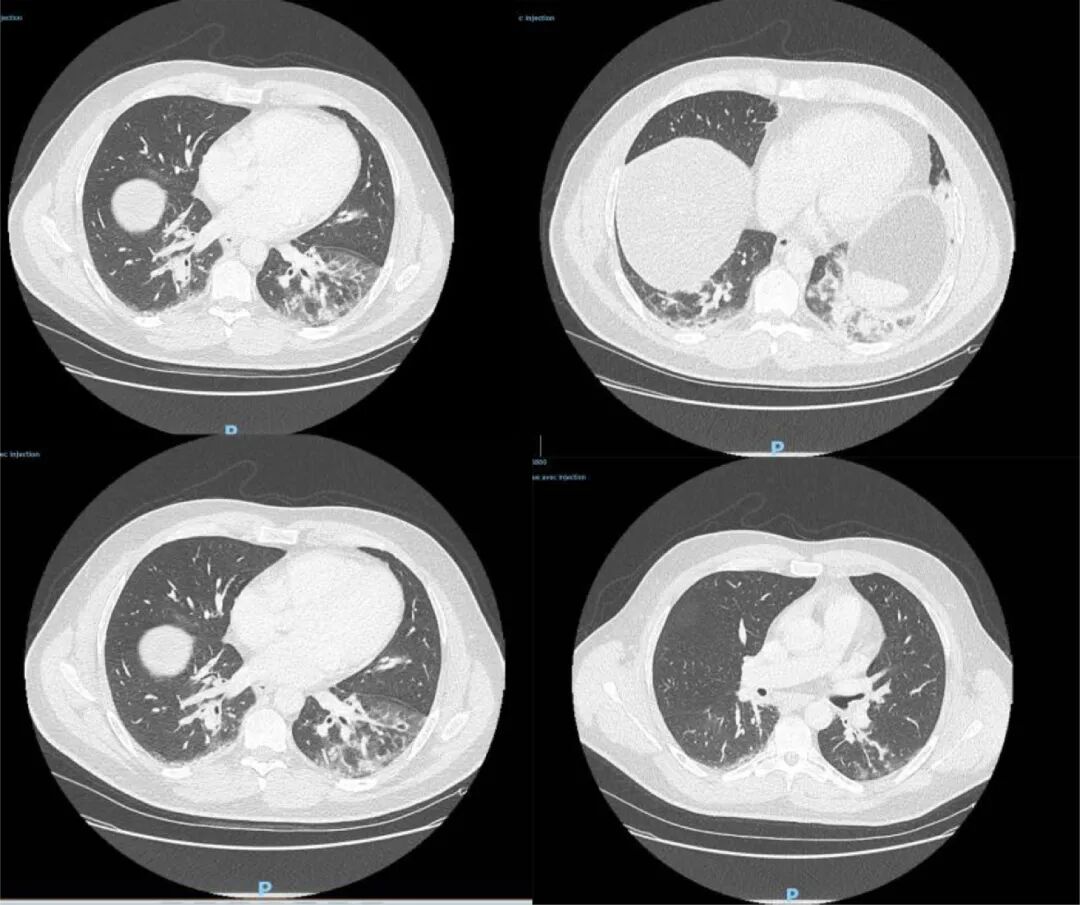

论文显示,研究人员选取了14个在2019年12月2日到2020年1月16日期间因类流感疾病(ILI)入住重症监护室的病例,研究人员发现,一名42岁男子的样本新冠病毒检测呈阳性。该男子出生在阿尔及利亚,已长居法国多年,职业为鱼贩,最近一次旅行是在2019年8月前往阿尔及利亚。他于去年12月27日到急诊室就医,CT检查显示双侧肺下叶呈现磨玻璃影,并伴有咯血、咳嗽、头痛及发热症状,且当时症状已持续4天。病患当天被收入重症监护室并进行抗生素治疗,后因病情好转于12月29日解除重症监护。

△图为病患CT检测影像

论文指出,由于这一病例与中国缺乏关联,并且在发病前没有临近旅行史,这表明新冠病毒2019年12月底已在法国人当中传播,比2020年1月24日官方首次确诊病例早了近1个月。由此也可推测,在2020年1月期间法国或存在大量无症状感染者,他们造成了病毒的进一步扩散。论文还称,这一发现改变了对于法国新冠肺炎疫情发展的认知,此前相应的研究模型需要就此作出调整。